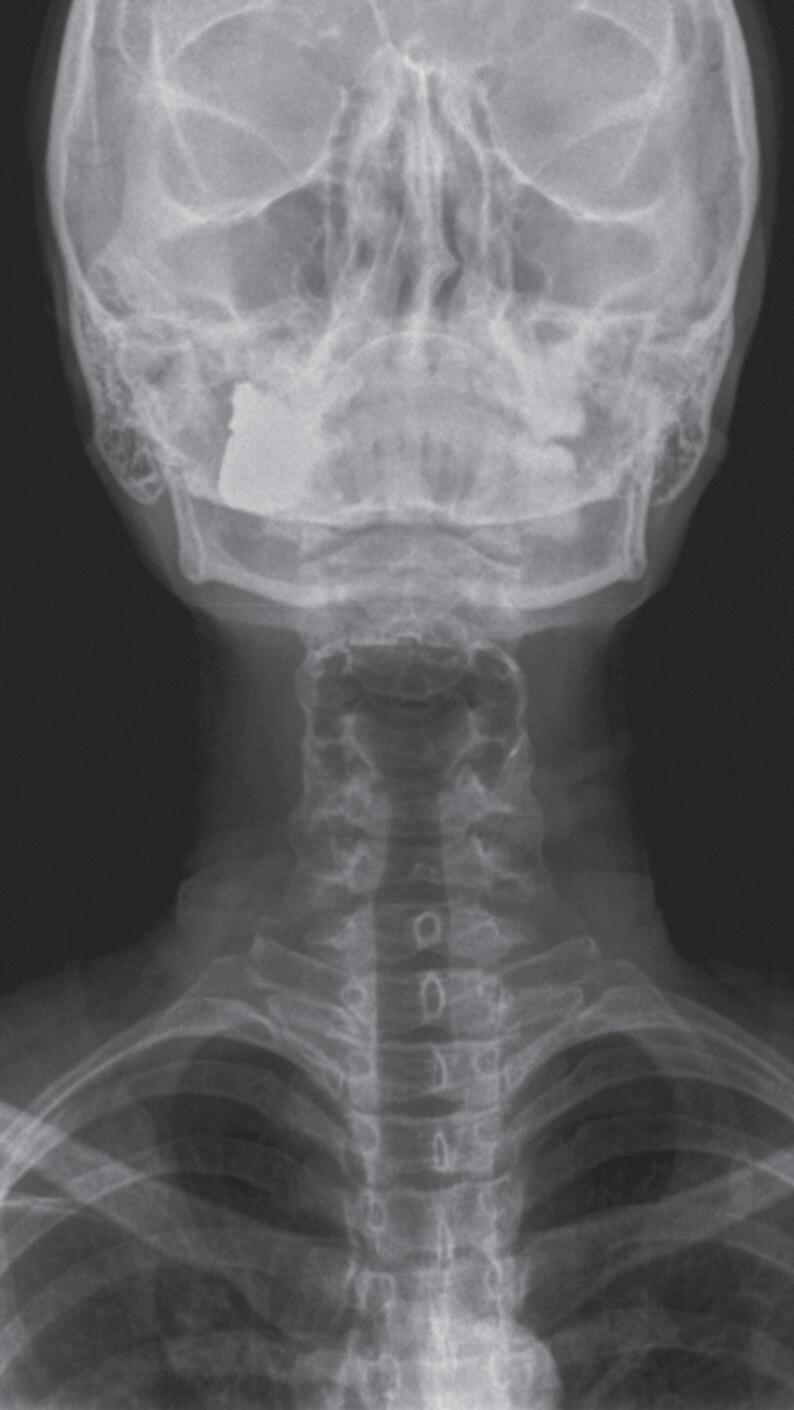

Fig. 1-1. Montagem de duas imagens radiográficas em visão anteroposterior demonstrando o percurso da deglutição desde a cavidade oral até o estômago (a) no adulto e (b) no bebê.

Fig. 1-2. Demonstração das estruturas envolvidas no processo da deglutição nas visões (a) lateral e (b) anteroposterior na imagem radiográfica.